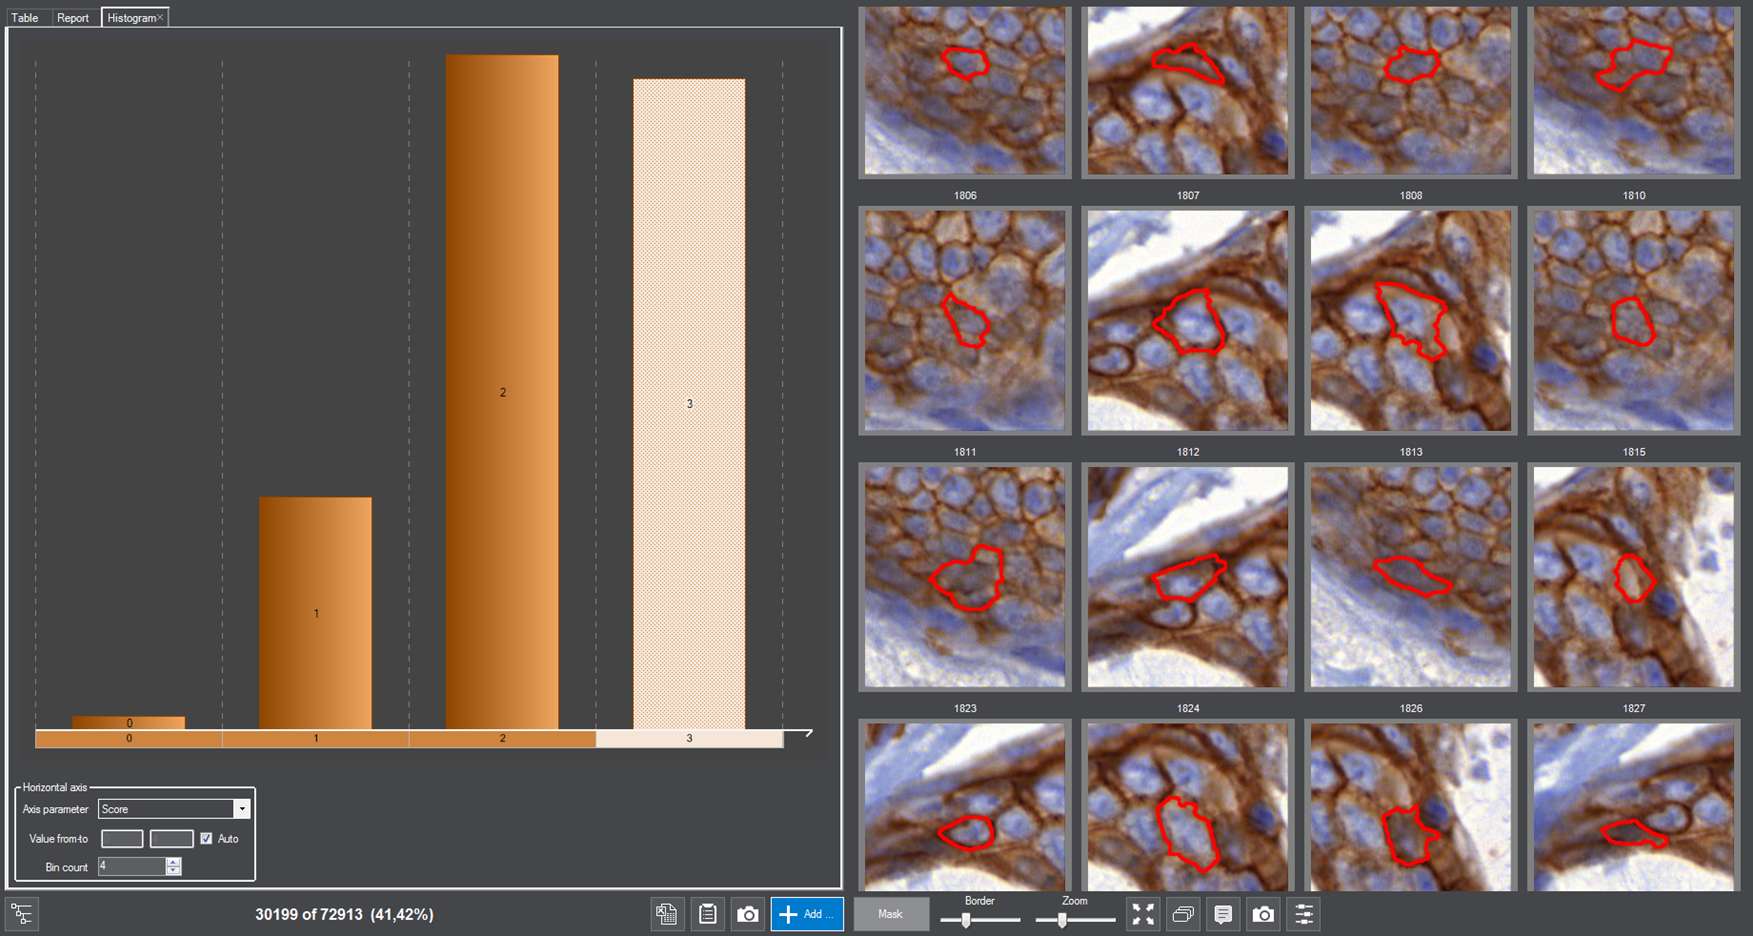

MembraneQuant is a cell membrane detection software application that can be used for the quantification of IHC stained histological samples. This module measures cell morphology and stain density, reports intensity-based core ranges, overall scores and positivity percentages (including H-Score), distinguishing the continuous membrane stain from the moderate stain.

This module has IVD approval for the quantification of Her2 expression in breast tissue samples.